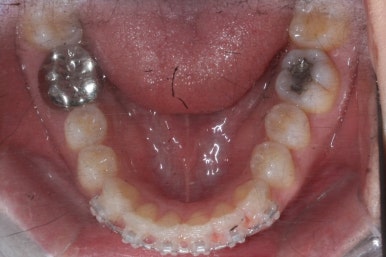

이번에는 약간 다른 양상으로 조절을 하기 위해서 MTA 장치 말고 일반 브라켓을 붙이기로 하였습니다.

이번에 사용한 장치는 클리피씨라고 하는 세라믹 자가결찰 장치였습니다.

그리하여 부산앞니교정 키다리아저씨치과에서 장치를 재부착하고 일종의 재교정을 들어갔습니다.

유지장치를 하지 않은 상태였기 때문에 원래대로 앞니가 되돌아간 것을 볼 수 있습니다.